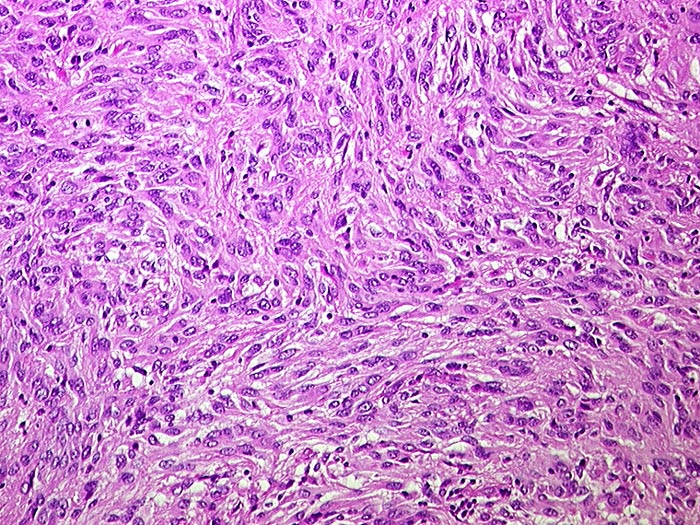

PathoPic ID 1089 - Gastrointestinaler Stromatumor (GIST)

Gastrointestinaler Stromatumor (GIST)

maligner Tumor

Dünndarm

Darm, Anus

Zellreicher mesenchymaler Tumor. Die spindeligen Tumorzellen zeigen geringgradige Atypien und bilden kleine Stränge mit unregelmässigem Verlauf.

Metastasen im mesenterialen Fettgewebe und in der Serosa. S-100 negativ, SM-Actin herdförmig positiv, CD 117 (c-kit) positiv.

Histologie